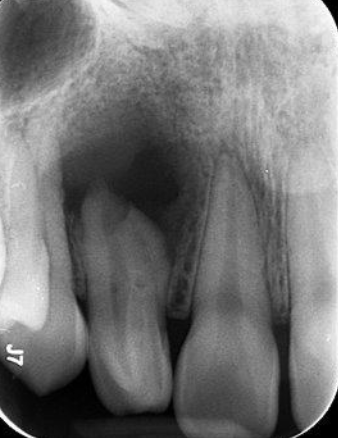

The first step to opening the access is to study the

Pre-operative radiographs and determine the depth of access from it

When creating your access in maxillary central incisors, what should you observe in your radiograph?

Anatomy, shape, and location of canal